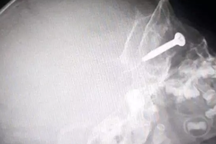

Lúc này gia đinh vội đưa ông đến Bệnh viện Đa khoa huyện Thạch Thất cấp cứu. BSCKI Nguyễn Đức Thảo, Trưởng khoa Ngoại tổng hợp, Bệnh viện Đa khoa huyện Thạch Thất cho biết bệnh nhân vào cấp cứu trong tình trạng có vết thương tại vùng bụng, đau bụng dữ dội... Sau khi thăm khám chụp X-quang và làm các xét nghiệm cần thiết, bác sĩ xác định có một dị vật cứng dài khoảng 3cm đã đâm xuyên qua da vào trong ổ bụng và gây thủng ruột non. Dị vật gây chảy máu trong ổ bụng dù vết thương bên ngoài da rất nhỏ.

Ca phẫu thuật kéo dài hơn 1 giờ. Ê kíp phẫu thuật đã lấy được dị vật ra khỏi ổ bụng là một thanh sắt dài khoảng 3,5 cm, đồng thời xác định được vị trí quai ruột bị dị vật đâm thủng. Bệnh nhân được khâu tổn thương bảo tồn ruột và được chuyển về khoa ngoại theo dõi và điều trị tiếp.